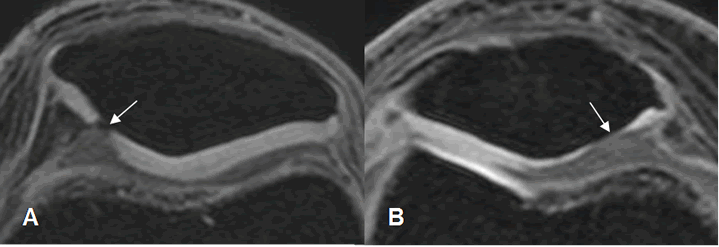

Fig 168. Condromalacia patelar grado 3.

A: RM axial en T2 y B: RM axial en 3D T1 STIR. Pérdida del cartílago articular a nivel del vértice, mayor del 50%.

Fig 169. Condromalacia patelar grado 3.

A y B: RM axial en 3D T1 STIR. Pérdida del cartílago articular, mayor del 50%.